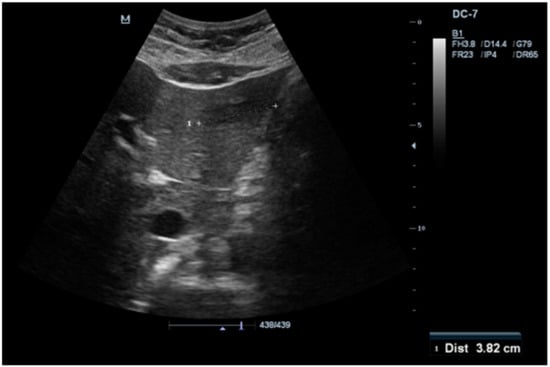

2. Case Report